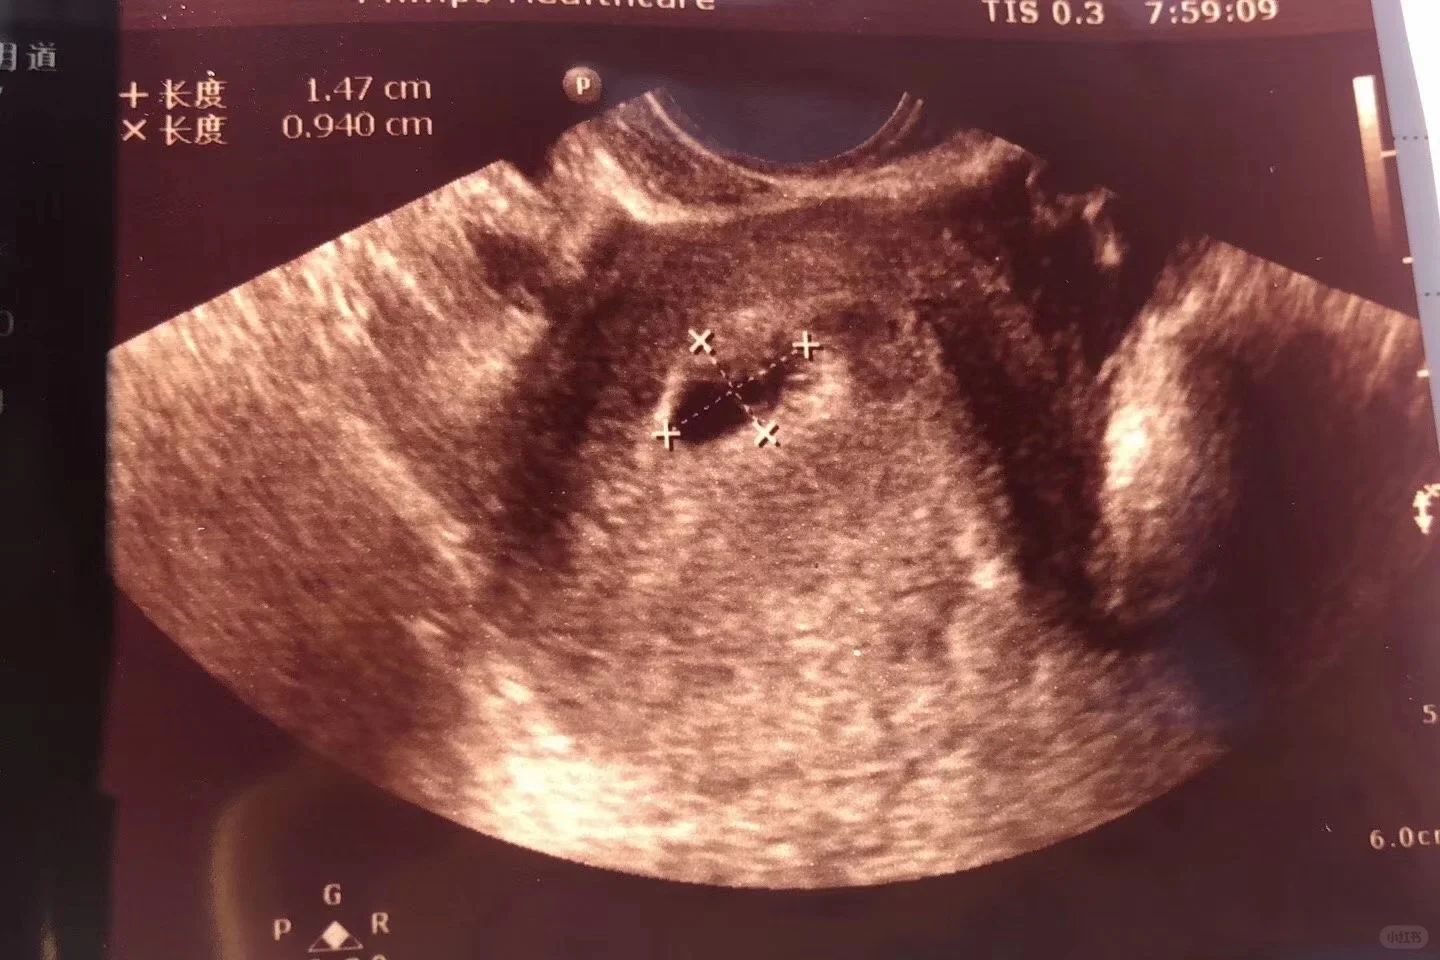

进周的时候我还是挂的王俊霞的专家号,先进行去一号楼一楼交材料,给我定的方案是拮抗剂方案。促排打的是果纳芬,果纳芬挺贵的,需要冷藏保存。每个人打果纳芬的量都不太一样,医生会根据检查情况开下一次的。刚开始打果纳芬需要两三天去医院抽血B超,后面每天都要去抽血B超。需要看卵泡发育情况,在这期间医生根据我卵泡...